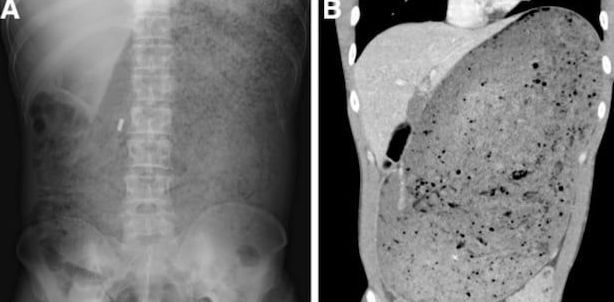

싱가포르의 한 남성이 햄버거를 30분 만에 3.2㎏을 먹은 뒤 응급실에 실려 갔다. 의학 저널 ‘위장병학(Gastroenterology)’

공개된 남성의 복부 CT 사진에는 배꼽 바로 위부터 어깨 부근까지 음식물로 가득 차 있는 모습이 고스란히 담겼다. 병원에서 복부 CT 촬영을 한 결과 A씨의 위와 십이지장은 섭취한 음식물로 인해 거대하게 늘어나 있었다.

소화되지 않은 음식물이 주변의 장기를 압박하며 췌장이 으스러져 있었다. 또한 혈액 속 총 백혈구 수와 혈청 크레아티닌, 혈청 아밀라제 수치도 심각하게 높았다.